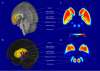

This atlas takes advantage of ultra-high resolution 7T MRI to provide unprecedented levels of detail on structures of the basal ganglia in-vivo. The ATAG atlas includes probability maps of the striatum, GPe, GPi, red nucleus, substantia nigra, subthalamic Nucleus(STh) and the PAG. The atlas has been created on 30 young (M:24.2), 14 middle-aged (M: 52.5), and 10 elderly (M: 69.6) participants.

Separately a STh atlas was created based on 13 young (M:24.38), 8 middle-aged (M:50.67), and 9 elderly participants (M:72.33).